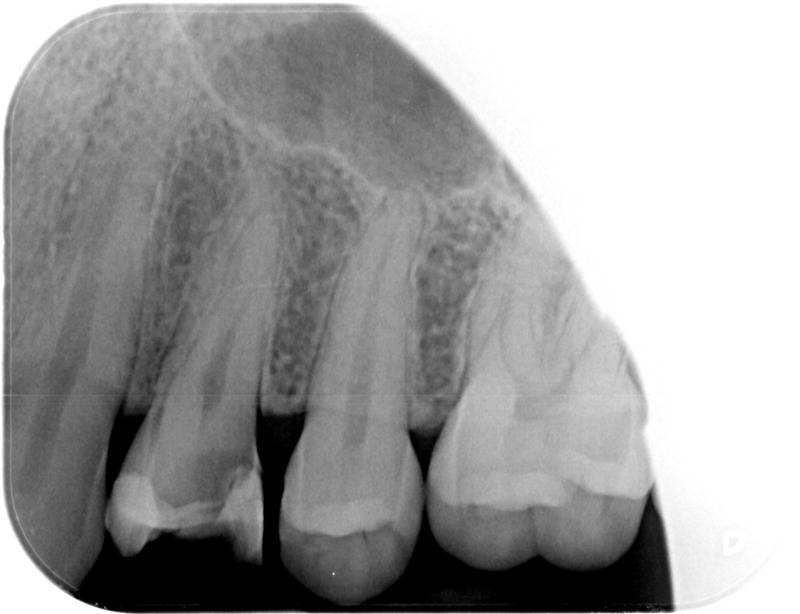

• Reprise de traitement endodontique : La manœuvre consiste à retourner à l’intérieur des racines d’une dent déjà traitée. Il arrive occasionnellement qu’une nouvelle inflammation se déclare suite à une reprise de carie ou une fracture de la dent, ou si le premier traitement endodontique est incomplet. Après s’être assuré que la dent lésée était conservable, il convient de désinfecter de nouveau le réseau canalaire parfois très complexe. La nouvelle obturation des canaux devra être protégée aussi rapidement que possible pour éviter une éventuelle contamination bactérienne.

Avant

Après